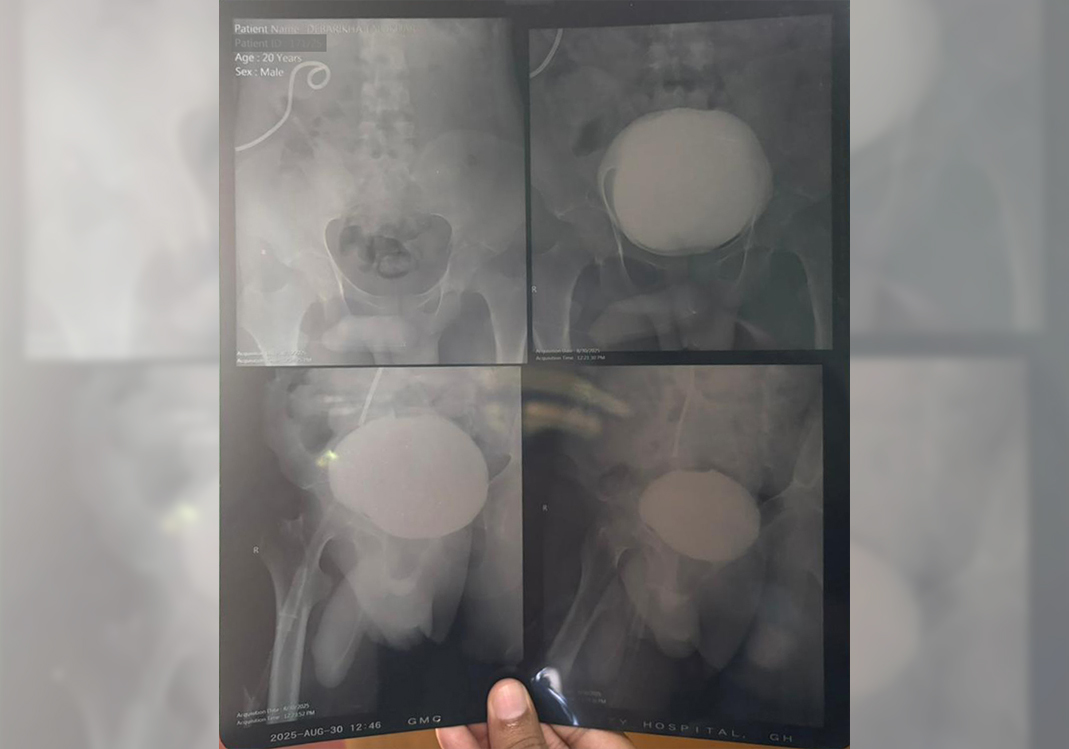

A tragic accident changed everything. A speeding tempo struck Debarshi, leaving him severely injured and fighting for his life. He was rushed to the hospital, where doctors saved him from the brink of death… but his kidneys were badly damaged.

Now, Debarshi is in urgent need of critical treatment to survive. The medical expenses are unbearable — his family, already struggling to make ends meet, has exhausted everything they had. Each day in the hospital brings new hope… but also new bills they simply can’t afford.